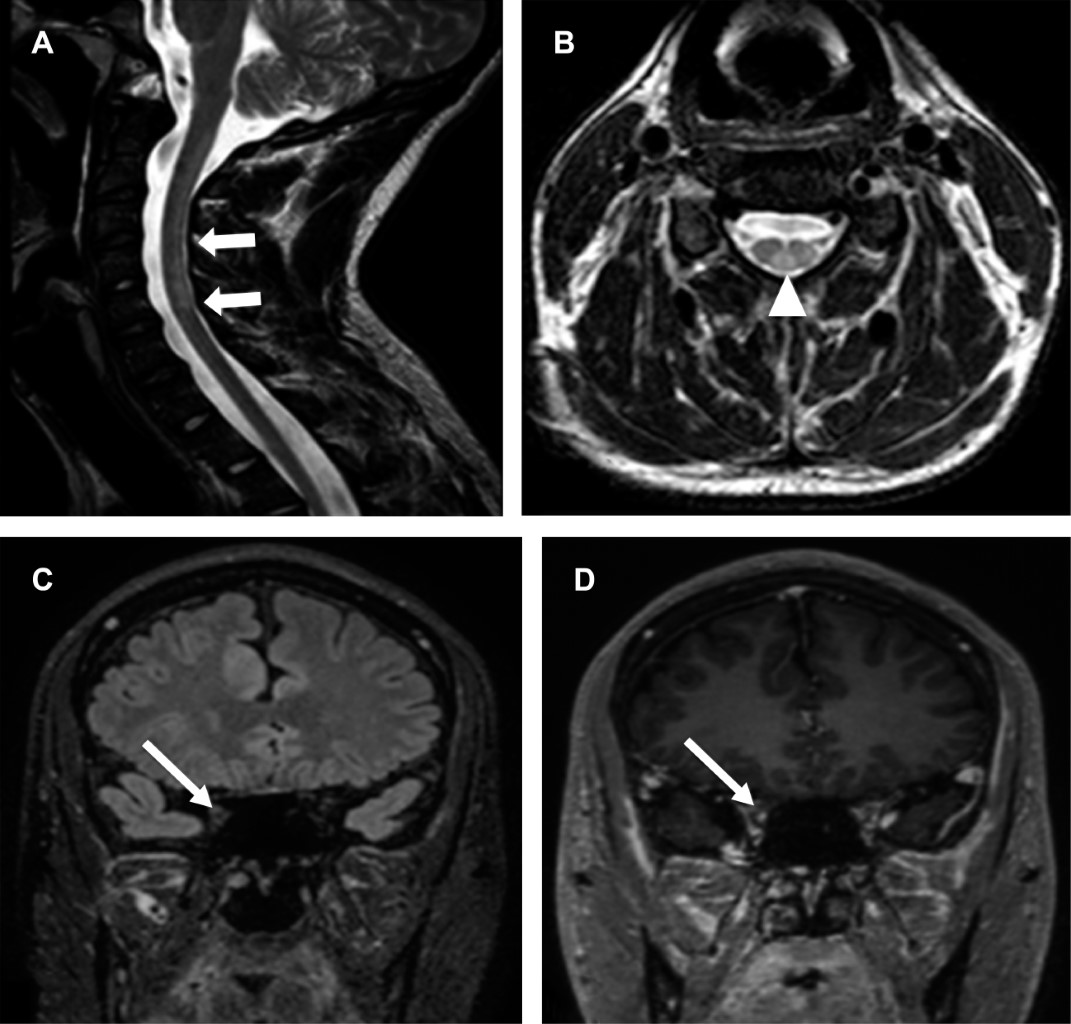

Masculino de 17 años con dos semanas de febrícula, cefalea, ataxia, disminución de agudeza visual de predominio derecho, temblor, fuerza disminuida en extremidades. Laboratoriales: leucocitos 10,100/mm3 con 75%N, proteína C reactiva (PCR) 41.2 mg/L, ELISA VIH negativo, tóxicos en orina negativos. Punción lumbar: leucocitos 70/μL (92% mononucleares), glucosa 68 mg/dL, sugerentes de EMDA, se realizó resonancia de ingreso (Figura 1); se descartó EM por negatividad de bandas oligoclonales IgG específicas, con positividad para anticuerpos anti-MOG mediante EBC. El tratamiento agudo se realizó con metilprednisolona intravenosa a dosis altas con discreta mejoría, en resonancia control presentó compromiso de médula espinal, así como de nervios ópticos (Figura 2); se adicionaron inmunoglobulinas, ocho meses después presentó mejoría sintomática. En resonancia de seguimiento para valoración de tratamiento con disminución de lesiones sin realce de las mismas (Figura 3).

La investigación de MOGAD ha avanzado rápidamente en los últimos años, aunado a la mejoría del conocimiento fisiopatológico y radiológico de la enfermedad por compromiso frecuente de neuritis óptica dada por el aumento de intensidad y realce en secuencias contrastadas, con predilección por la vía óptica anterior.2 En aquellas con fenotipo EMDA revelan múltiples lesiones hiperintensas en T2 de gran tamaño y mal delimitadas en la sustancia blanca, la sustancia gris profunda, el tronco encefálico o los pedúnculos cerebelosos medios. Así como en la MT, la resonancia típicamente muestra lesiones hiperintensas en T2 longitudinalmente extensas en las imágenes sagitales que se ubican en centro de imágenes axiales, a veces restringidas a la sustancia blanca o una mezcla de las manifestaciones anteriores mencionadas, convirtiendo a la resonancia en la imagen de elección para tal fin en el diagnóstico, vigilancia y control de la enfermedad.1

Figura 1

Figura 2